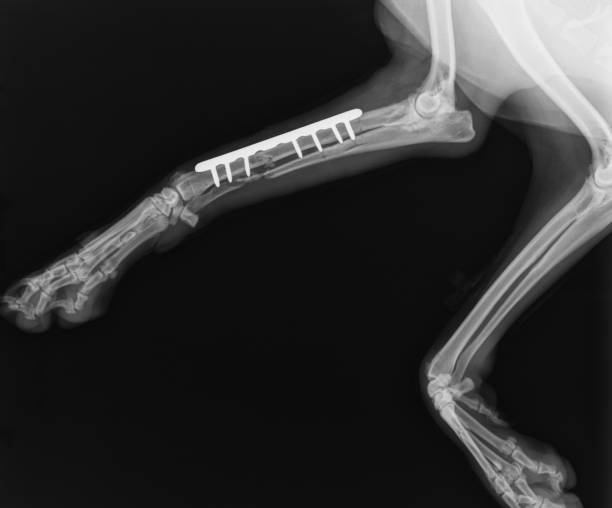

Fracture-

If unfortunately you pet has fracture and confirmed with x-rays then surgery is done to reduce the both fracture ends with the help of plate/screws or pins.